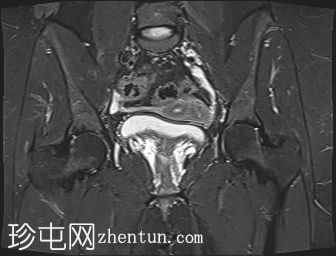

轴位

STIR序列

子宫外底轮廓清晰,肌层较厚,将子宫内膜腔分隔成两个腔,纤维层较薄,向下延伸至宫颈外口。子宫内膜厚度正常,两个子宫腔交界区清晰,未见明显的实性局灶性病变。

卵巢卵泡形态正常,可见多个小卵泡,主要位于卵巢周边,无优势卵泡。未见实性或囊性肿块。

膀胱MRI表现正常。

未见盆腔软组织肿块或淋巴结肿大。

未见明显盆腔游离积液。

本病例展示了典型的纵隔子宫影像学表现:增厚的肌层隔膜将子宫内膜腔分隔成两个腔,并有一层薄的纤维隔膜延伸至子宫颈外口水平,符合完全纵隔子宫的特征。

纵隔子宫是最常见的先天性子宫畸形,可能导致流产率升高。

磁共振成像(MRI)是目前首选的影像学检查方法。

在MRI图像上,纵隔子宫通常大小正常,但每个子宫腔的形态均小于正常子宫腔。

隔膜可能由纤维组织(T2信号低)、肌层组织(中等信号)或两者共同构成,如本病例所示。